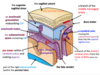

Structure A is a branch of which artery

Name structures A and B

Name structures A-D

What type of haemorrhage is this?

Q

22

Subarachnoid

Name structures A-C

Name structures A and B and which bone of the skull they are a feature of

Describe which structures could be found at areas A-C

Name the bony structures A-D

The groove at A is found between which two bones of the skull? What structure would run within this groove?

Name artery pairs A-F

Name structures A-D